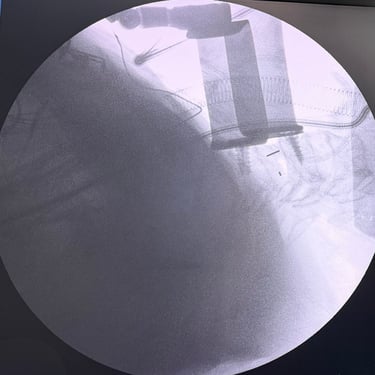

Hernia Cervical con Mielopatía: ACDF con Cage y Placa asistida con Monitoreo Neurofisiológico

La hernia cervical con mielopatía se produce por la compresión de la médula espinal, ocasionando dolor cervical, debilidad, alteraciones sensitivas y trastornos de la marcha. En casos de compromiso neurológico progresivo, la discectomía cervical anterior y fusión (ACDF) con cage y placa es una alternativa quirúrgica eficaz. La cirugía asistida con monitoreo neurofisiológico intraoperatorio permite evaluar en tiempo real la función neurológica, aumentando la seguridad del procedimiento. Este abordaje facilita una descompresión adecuada, estabilización del segmento cervical y favorece una recuperación neurológica segura y progresiva.